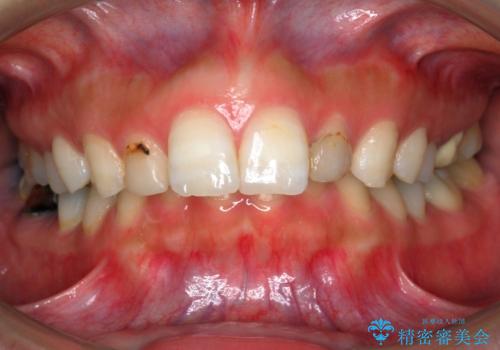

大人の出っ歯 がたがた 劇的に改善

- 前歯のがたがたを主訴に来院。

前歯がかなり大きかったため、ディスキングを行いました。

上下の小臼歯を抜歯しています。

臼歯は2級咬合であり、歯冠の高径が小さくブラケットを装着するのがかなり難しかったので治療初期はバイトアップを行いました。そのため、治療途中に青いレジンが下顎についていますが、途中で撤去しました。

また、上顎側切歯が中前歯よりも幅径が大きく、出っ歯になりやすい状態だったため、ディスキングにより前歯部の上下の歯の比率を揃え、しっかり咬むように工夫しました。